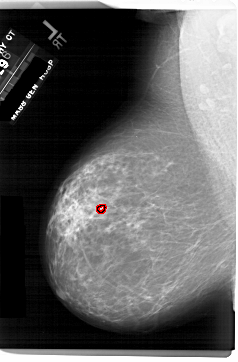

A_1743_1.RIGHT_MLO

RIGHT_MLO LINES 6526 PIXELS_PER_LINE 3811 BITS_PER_PIXEL 12 RESOLUTION 43.5 NON_OVERLAY

FILE: A_1743_1.LEFT_MLO.OVERLAY

TOTAL_ABNORMALITIES 1

ABNORMALITY 1

LESION_TYPE CALCIFICATION TYPE PLEOMORPHIC DISTRIBUTION CLUSTERED

ASSESSMENT 4

SUBTLETY 2

PATHOLOGY BENIGN